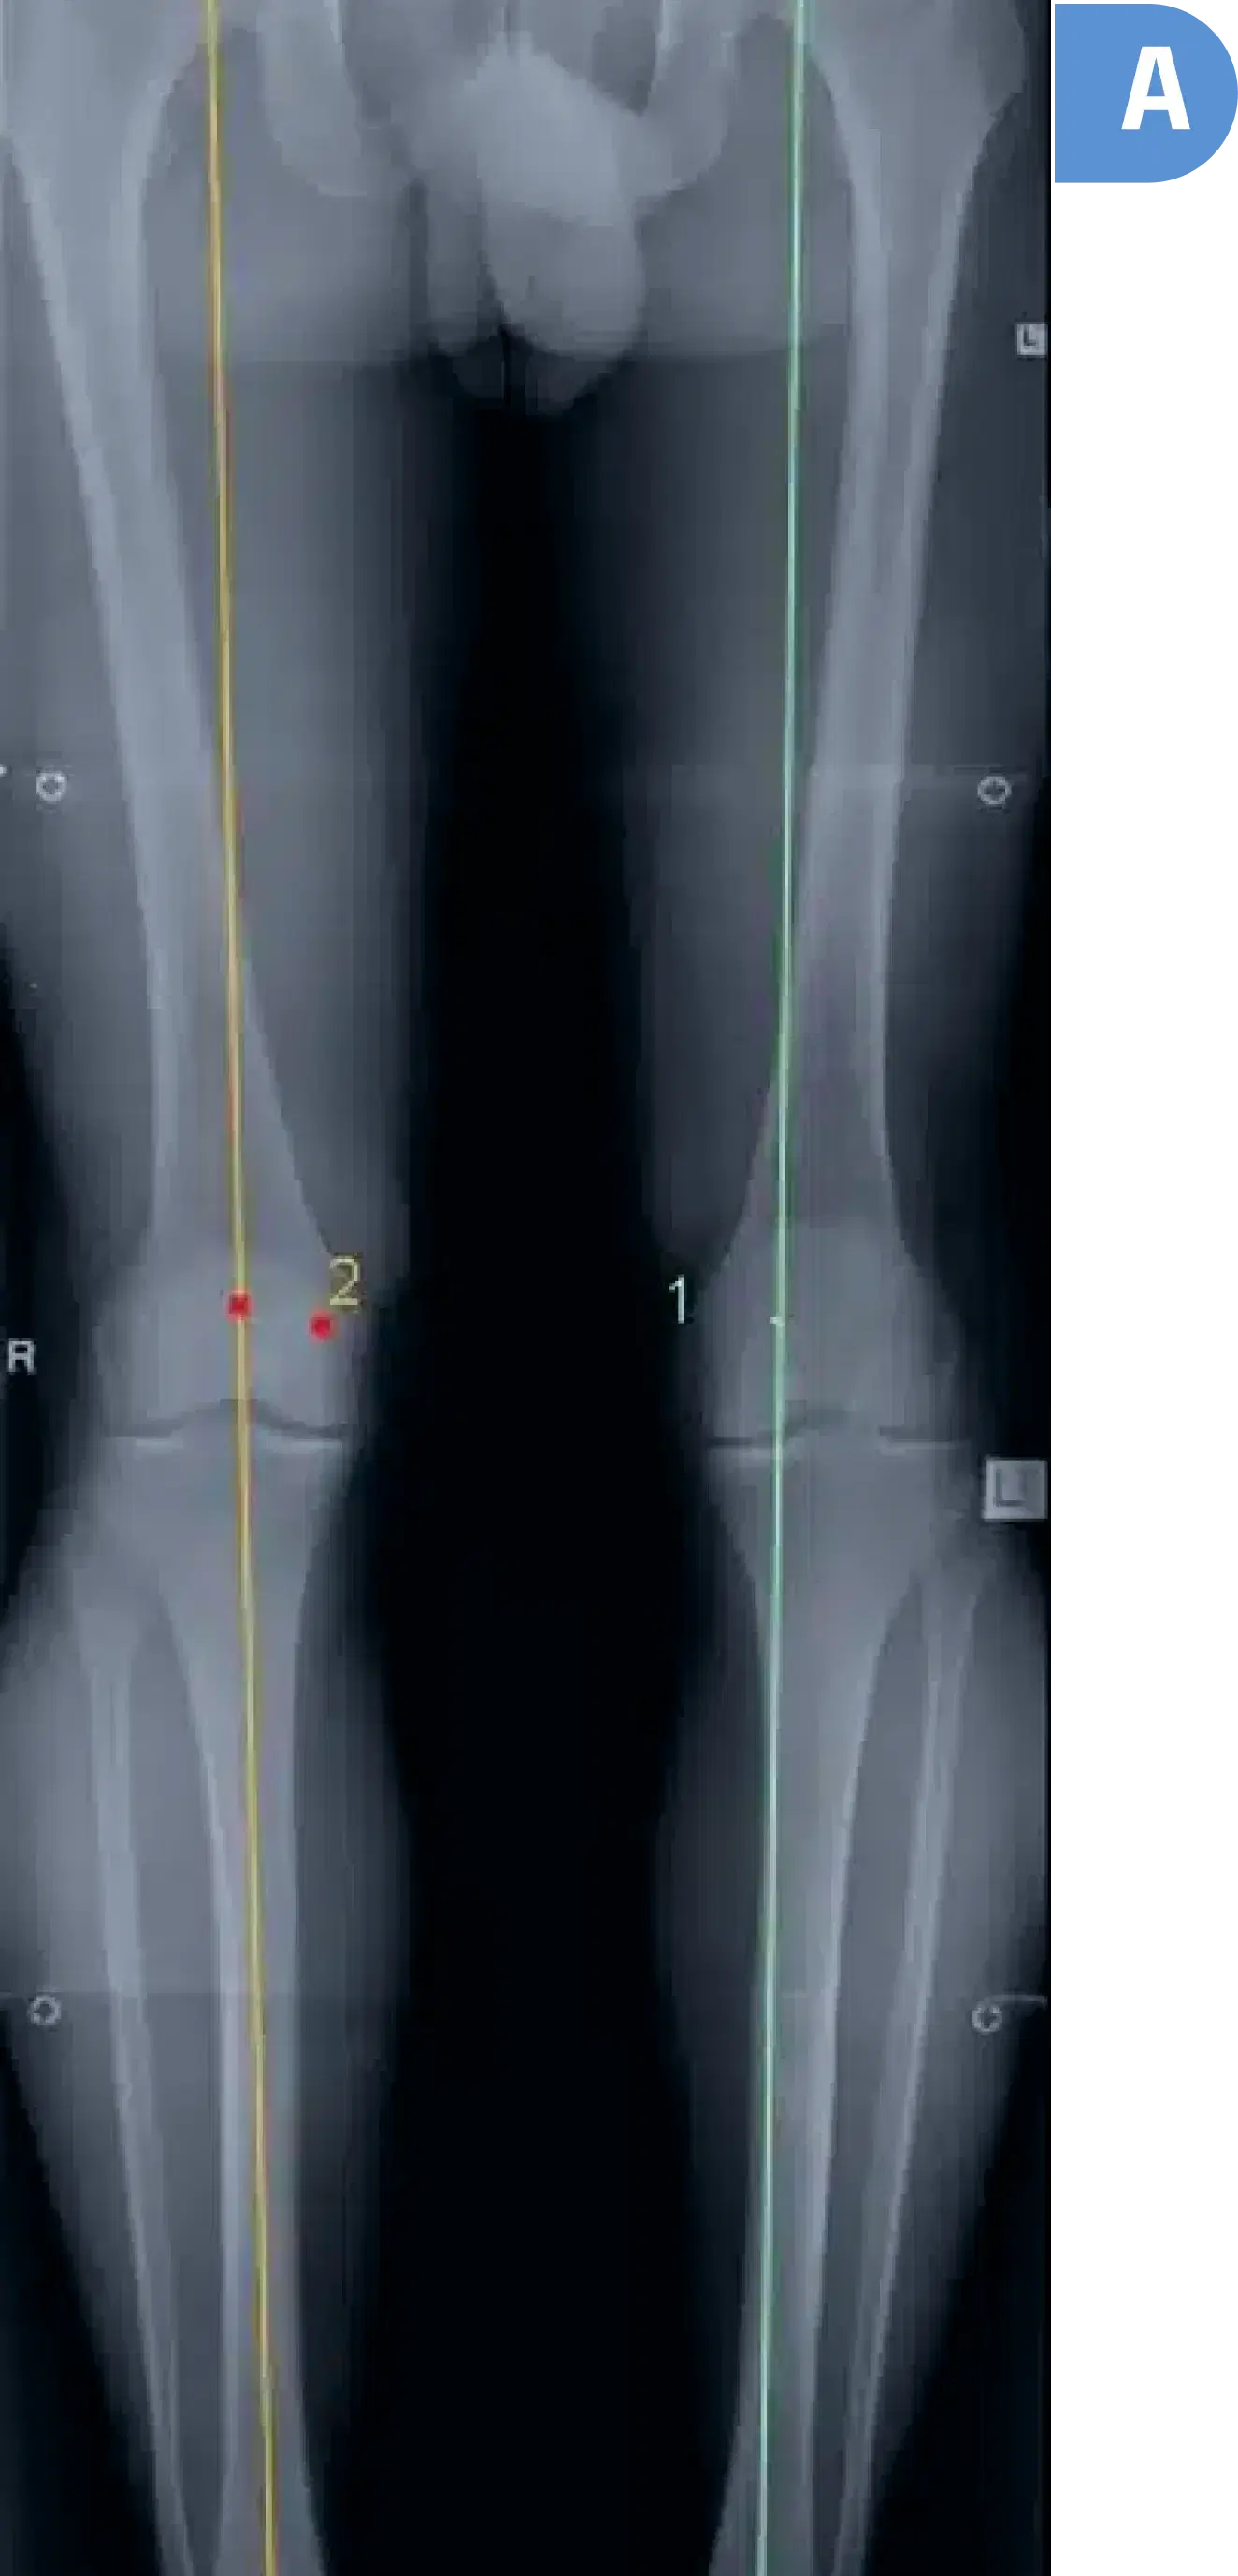

You will require a special long x-ray from taken from your pelvis to your ankles whilst you are standing. This x-ray helps calculate where most of the load is distributed in your knee, the severity of the deformity affecting the knee as well as the degree of correction required to unload the diseased part of the knee.

Pre surgery four-foot standing X-ray showing axis of right leg through the middle of the knee. Axis of left leg through the inner side of the knee (where the diseased cartilage is located)

A

Some x-ray facilities may lack the required cassette length for a "standing four foot leg x-ray." Check with the facility first. Dr. Seeto's office can suggest suitable facilities with the necessary equipment.